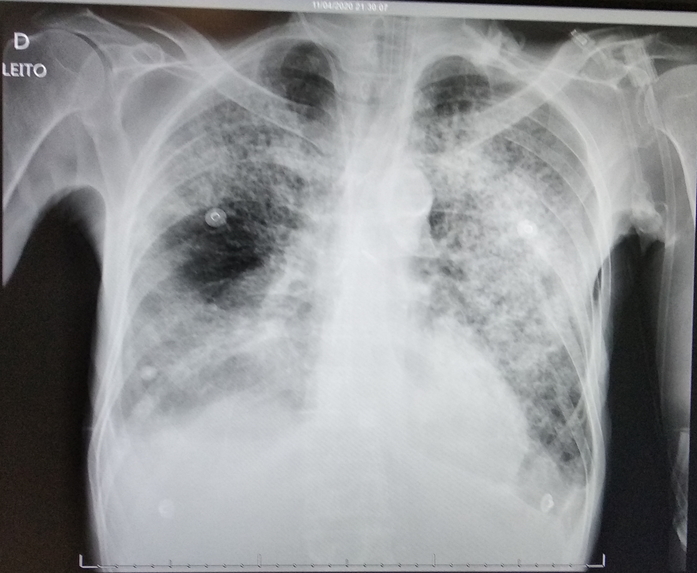

Demanda: Estudo de Caso Clínico (qual o meio de obte-lo: contrato NDA, orçamento?) das análises que fizemos (em anexo) de raio x e tomografia computadorizada obtidos em base pública realizado sob plataforma pública de deep learning com modelo abastecido por datasets públicos de pacientes suspeitos de contágio com covid-19 e outras doenças respiratórias****.

3 - Treinar o Modelo Mellieri Human de Rede Neural Convolucional para detectar o COVID-19 e outras doenças respiratórias em imagens de raios-X e tomografia computadorizada.

4 - Notamos que um paciente pode ter um misto de complicações respiratórias (Covid e Pneumonia por exemplo).

Qual impacto disto nas pesquisas e soluções para combate ao covid-19 como vacinas em função do estágio da doença a exemplo do metadados anexos já que os diagnósticos podem ser únicos para cada paciente no tempo?

Nota: Algumas bases de dados receberam aumento de dados (Data Augmentation) na ausência de um amplo dataset, curiosamente, antes da pandemia atingir o pais 70/80% dos óbitos eram grupo de risco com problemas cardíacos, ao passo que o diagnóstico com emprego de deep learning detect congestive heart failure já é obtido com um único batimento cardíaco de forma que uma única chapa ou tomográfica computorizada, independentemente do estágio, desde que seja positivo covid-19 pode ser empregado como dataset para emprego global de casos, o que não exclui a importância do diagnóstico amplo e diverso a exemplo de casos que combinam covid-19 e outras patologias respiratórias ***